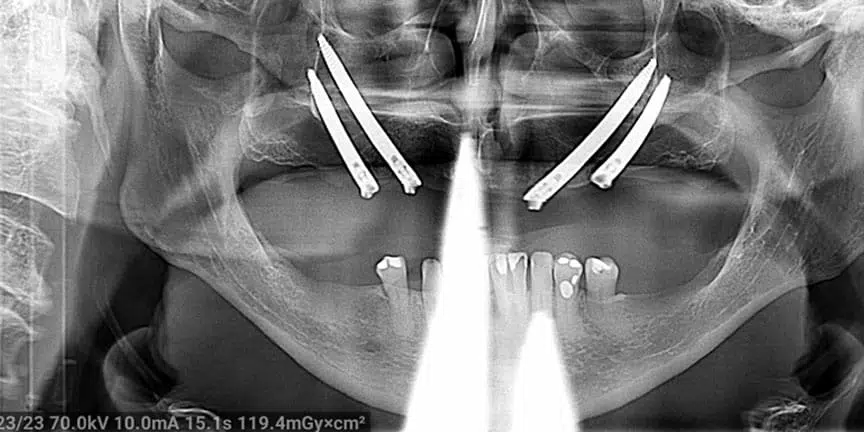

Challenging Cases

- We provide treatment for patients when other providers are unable to handle their cases.

Severe Bone Loss